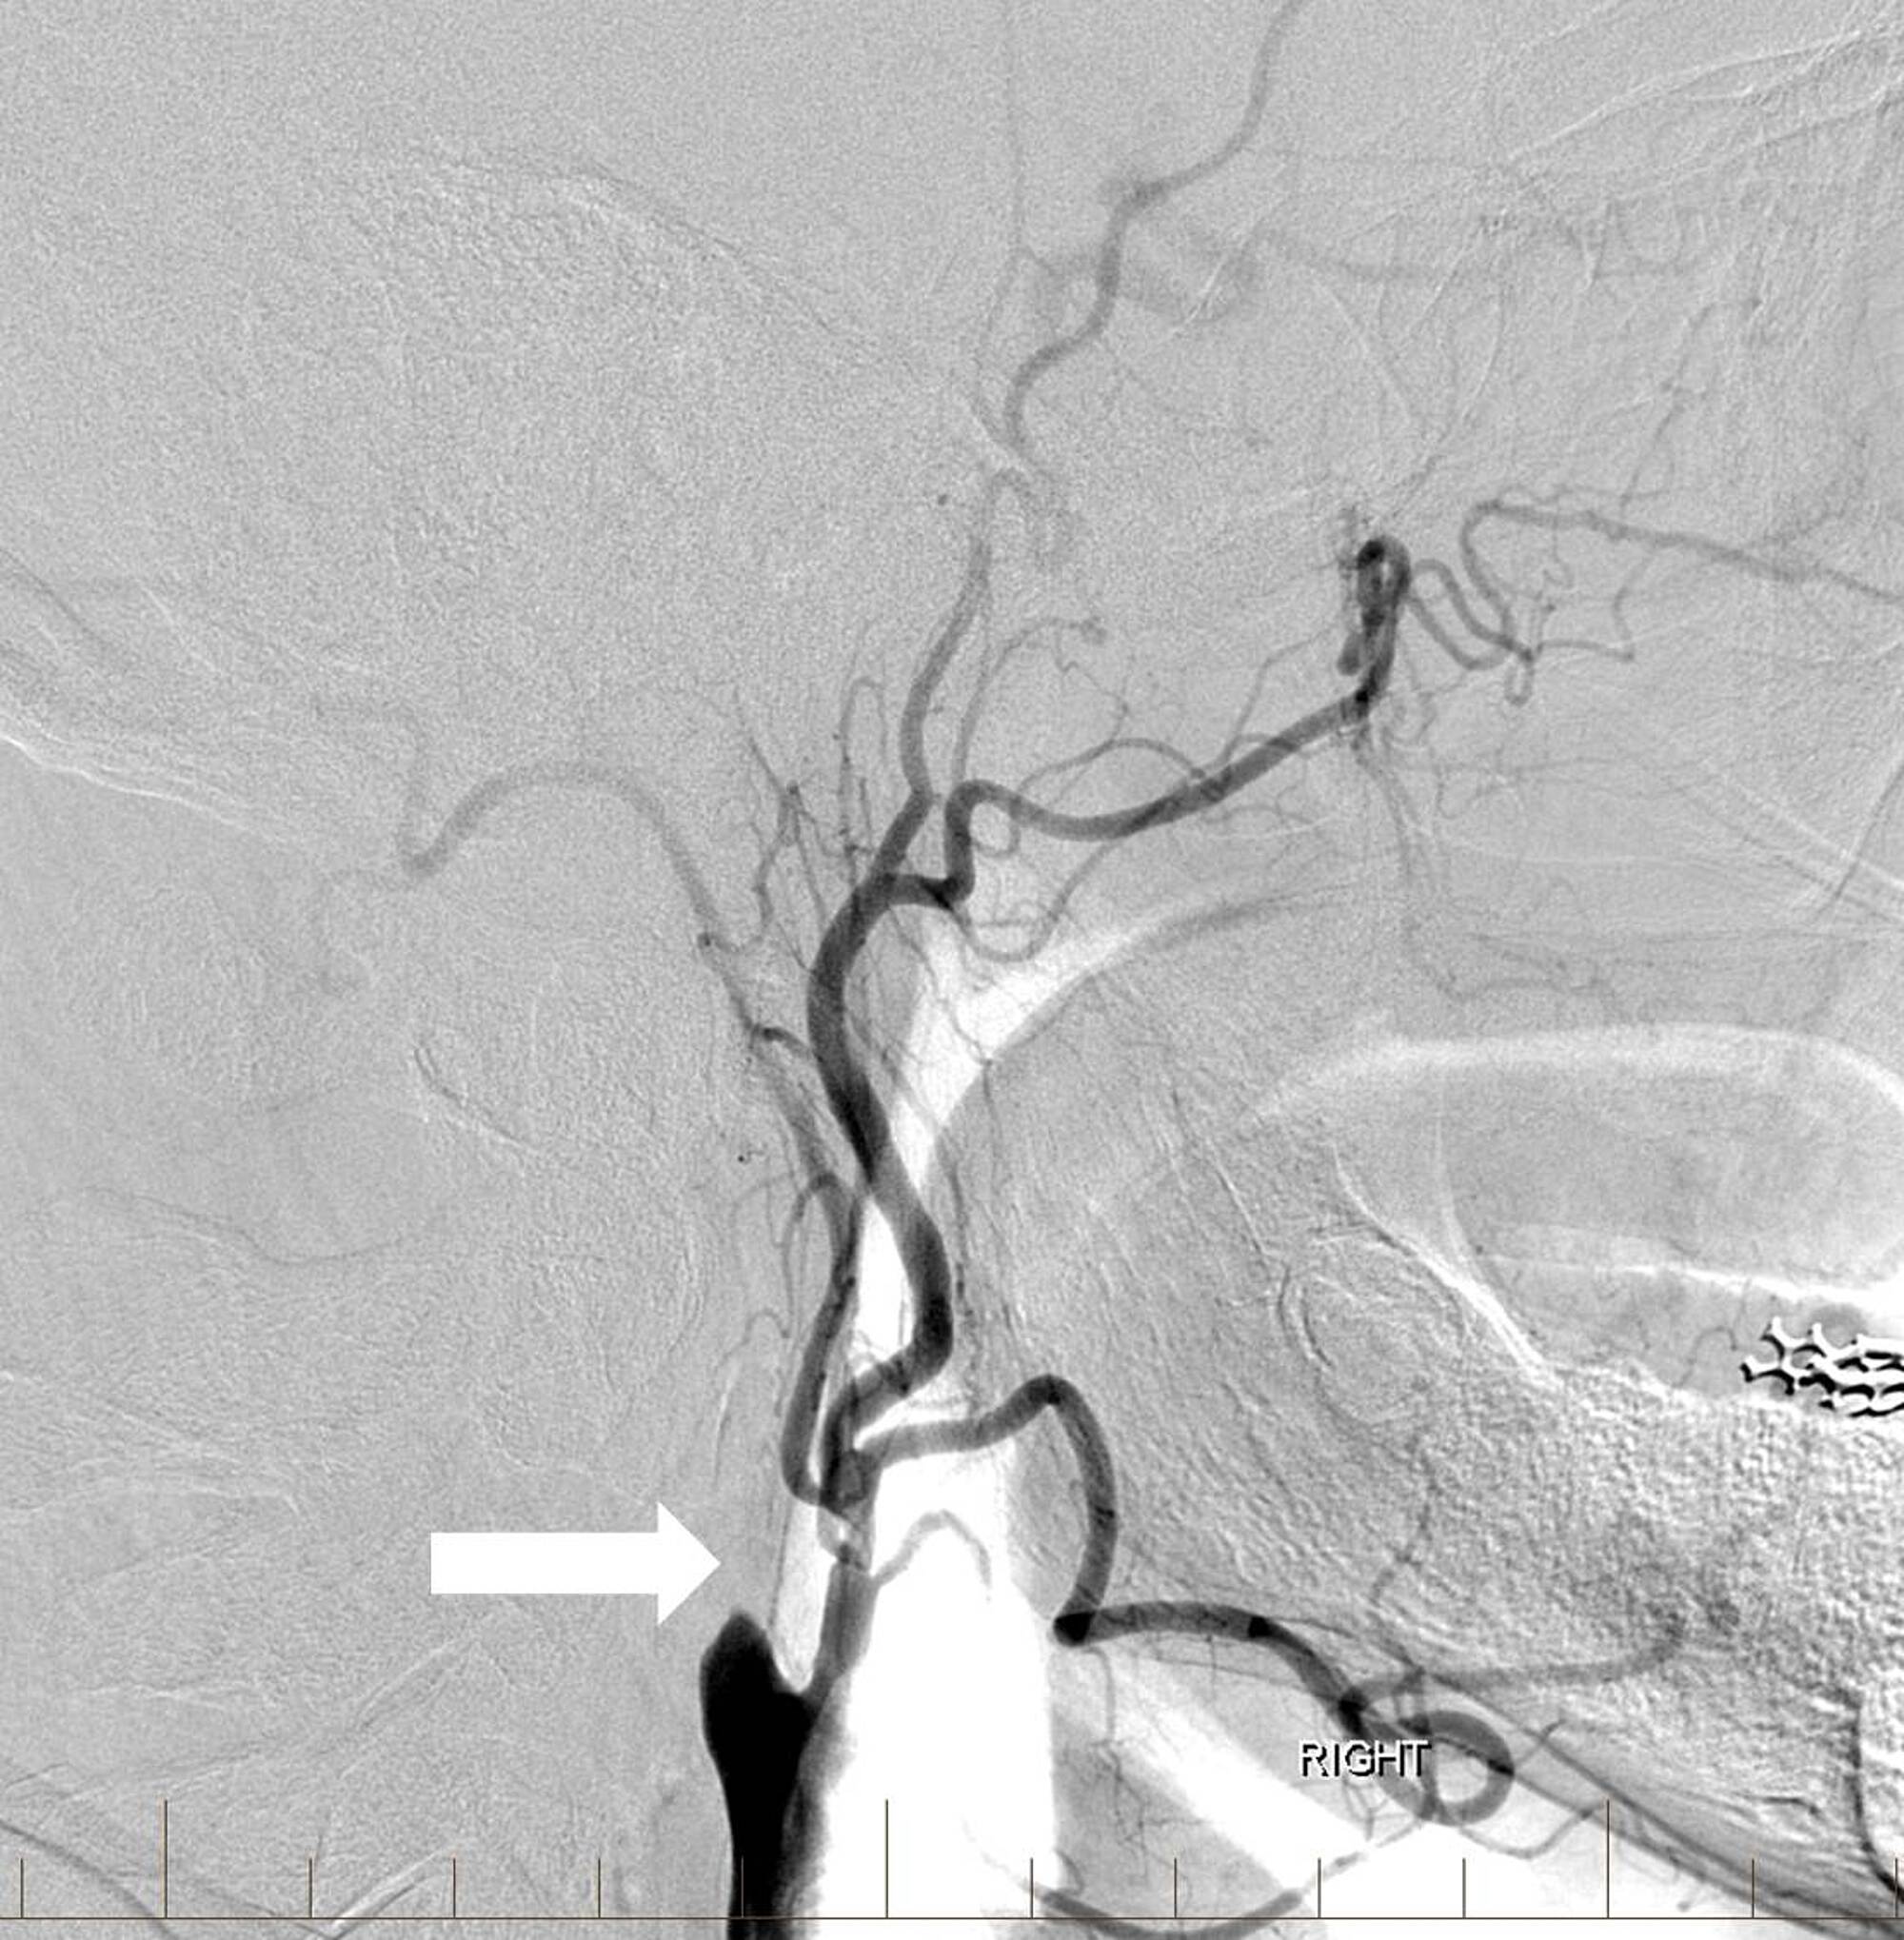

A 63-year-old man with a history of hypertension, hyperlipidemia, peripheral artery disease, smoking, and Stage IV lung cancer presented with left-sided weakness and dysarthria when he visited our institution for a chemotherapy port placement. His National Institutes of Health Stroke Scale (NIHSS) score was six and he was not a candidate for intravenous (IV) thrombolytics. Computed tomography angiography (CTA) revealed occlusion of the extracranial right internal carotid artery (ICA) and right middle cerebral artery (MCA) but no hemorrhage or large areas of acute ischemic change. Biplane digital subtraction angiography (DSA) revealed tapering to occlusion of the proximal right cervical ICA at the level of the carotid artery bulb (Figure 1).